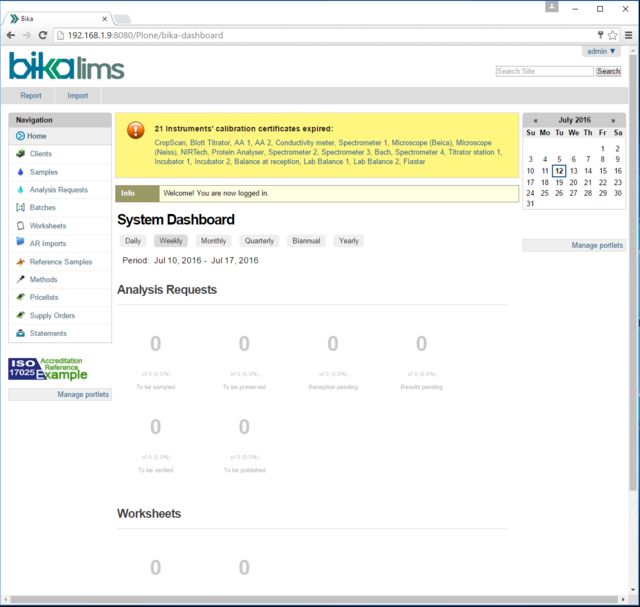

2. Laboratory Information Management System

- 1 x BikaLIMS LIMS Server, installed on Ubuntu 16

- LIMS: Laboratory Information Management System

- LIMS (Laboratory Information Management System):

- Wikipedia page : https://en.wikipedia.org/wiki/Laboratory_information_management_system

- BIKA LIMS: http://www.bikalabs.org/